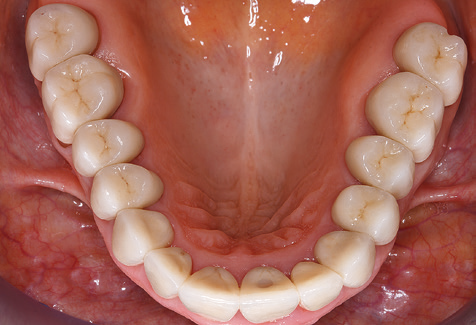

Standardised and regular risk-adapted care in the scope of SPT is the key to treatment success for the clinical long-term success in periodontically compromised patients. This is particularly true for patients fitted with implants following successfully completed periodontal treatment (Fig. 11a and b).

Fig. 9: The accessible implant and tooth surfaces are polished with polishing cups and suitable polishing compounds. – Fig. 10: Repeat instruction in the use of appropriate aids for oral hygiene at home should also form part of SPT. – Fig. 11a and b: Clinical situation 12 years after insertion of the prosthetic restoration. During this period, only a veneering ceramic fracture on tooth 47 and the requirement for endodontic treatment of tooth 12 were observed. All restorations are still functioning as intended.